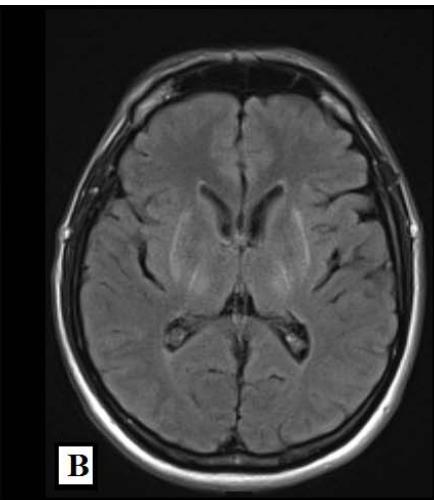

We report a rare case of Wilson’s Disease with neurologic features in a 31-year-old man. This disease consists of a disturbance of copper metabolism secondary to a mutation in the gene responsible for encoding the tissue transporter and the enzyme that incorporates the excess element into bile, generating toxic accumulation in the liver, cornea, and central nervous system. According to his wife, the patient had been treated for an unspecified mood disorder. The clinical picture was characterized by depressive mood, anhedonia, and anxiety. He had his first seizure episode on December 3rd, 2021. He progressed with dysarthria, ataxic gait, dystonia of the right-hand flexor muscles, and intermittent urinary incontinence. Marked worsening was observed after the diagnosis of COVID-19 in February 2022. At the clinical evaluation on March 24th, risorius muscle dystonia (risus sardonicus), resting tremor, and Kayser Fleischer rings at slit-lamp examination was also noted.